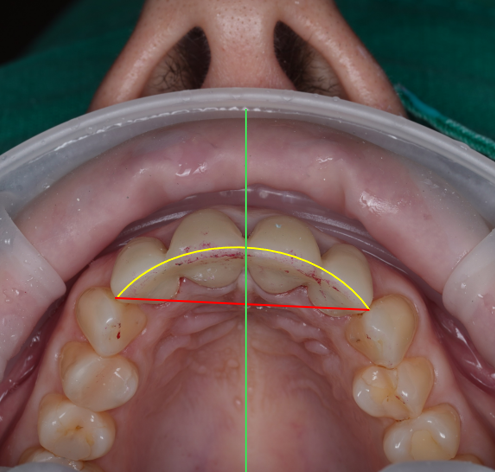

| 5) 얼굴과 치아 축의 틀어짐 |

이렇게 봤을 때 잘 모르실 수도 있는데요.

이렇게 선을 그어보면 틀어진 축을 볼 수 있습니다.